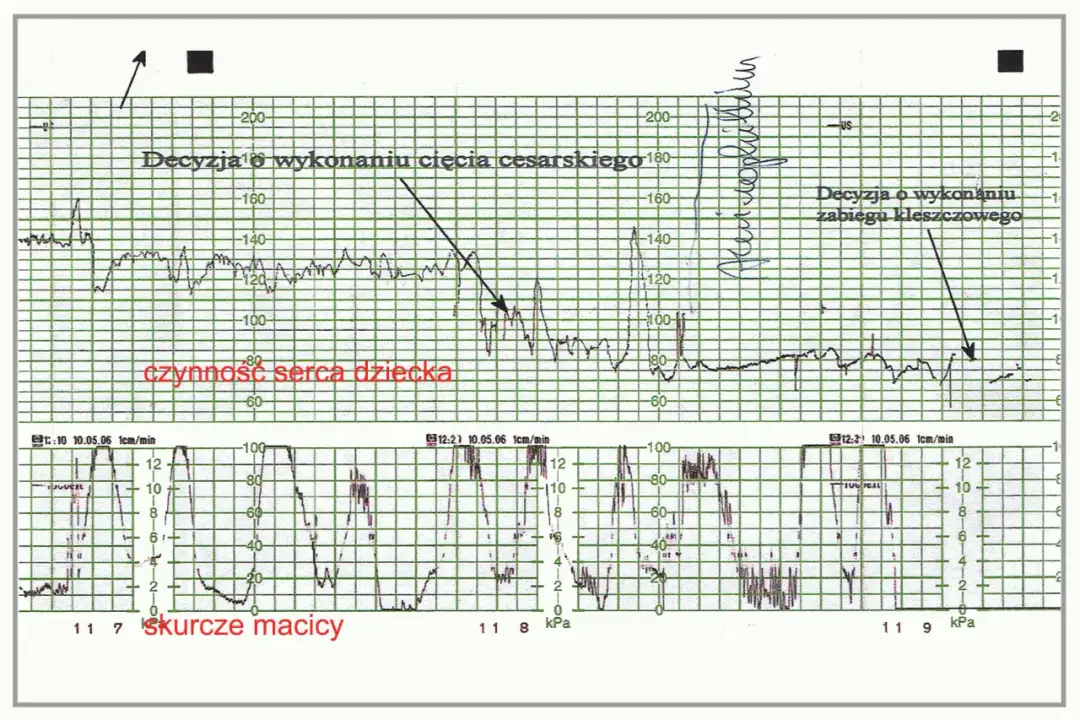

Skurcze macicy (UC) są oznaczane w zapisie KTG i ich analiza jest istotna dla oceny przebiegu porodu. Warto znać metody pomiaru skurczów, które są zazwyczaj wyrażane w jednostkach Montevideo (MVU) lub milimetrach słupa rtęci (mmHg). Jak interpretować te wartości? Częstość oraz intensywność skurczów dostarczają informacji o postępie porodu oraz reakcji płodu na te zmiany.

Podczas analizy skurczów macicy, kluczowe jest ich rozpoznanie na monitorze. Zidentyfikowanie wzorców skurczów oraz ich wpływu na tętno płodu pomaga w ocenie dobrostanu zarówno matki, jak i dziecka. W przypadku nieprawidłowości w skurczach, lekarze mogą podjąć decyzje dotyczące dalszego postępowania.

W trakcie analizy zapisu KTG istotne jest rozpoznanie wszelkich nieprawidłowości, które mogą wskazywać na problemy zdrowotne. Utrzymujące się odchylenia od normy, takie jak długotrwała bradykardia lub tachykardia, są sygnałem do dalszej diagnostyki. Niezwykle istotne jest, aby nie ignorować tych alarmujących oznak, gdyż mogą one sugerować niedotlenienie płodu.

W przypadku wykrycia nieprawidłowości lekarz podejmie decyzje odnośnie ewentualnych interwencji medycznych, które mogą obejmować cesarskie cięcie czy inne działania mające na celu poprawę stanu zdrowia płodu. Ważne jest, aby mieć świadomość, że wczesne rozpoznanie problemów zdrowotnych znacznie zwiększa szansę na pozytywne rezultaty.